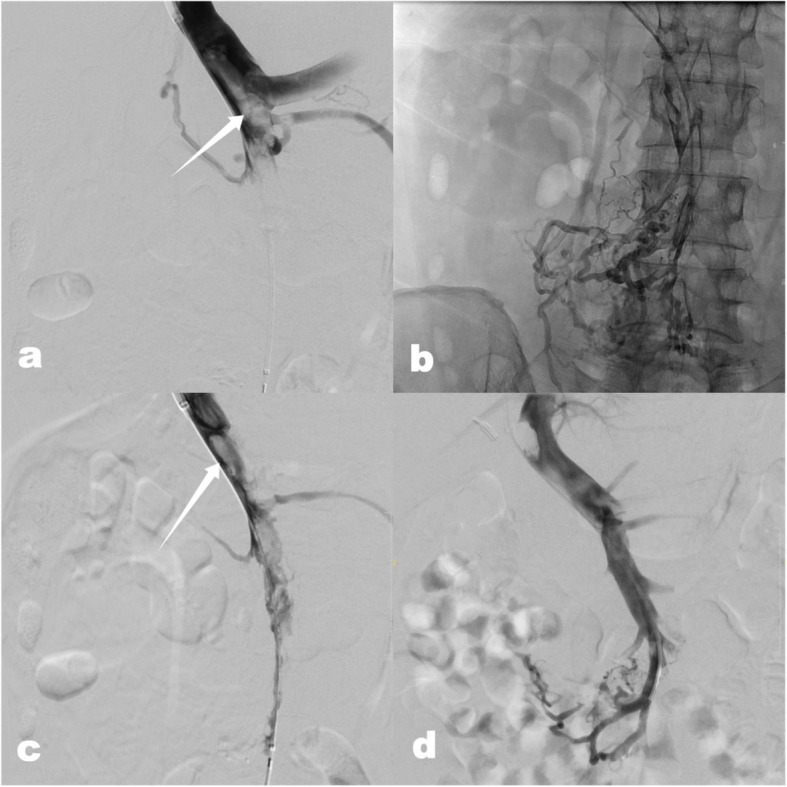

Methods: Between August 2019 and May 2024, 12 patients (males = 9; mean age, 52.33 ± 12.51 years) were diagnosed with ASMVT. The study collected comprehensive data on demographic details, presenting symptoms, etiology, treatment modalities, response to treatment, and follow-up outcomes. Computed Tomography (CT) was available from diagnosis, and an average of 6.3 CT scans with a median follow-up of 3 months (IQR: 2-20 months).

Results: The average time from symptom onset to angiographic treatment initiation was 8.0 ± 4.71 days, preceded by anticoagulation with heparin from the time of diagnosis. Patients were treated with combination therapy involving endovascular thrombolysis, rheolytic thrombectomy, and balloon angioplasty via transjugular (n = 9, 75%) or percutaneous (n = 3, 25%) approaches. Thrombolysis was performed with an average recombinant tissue plasminogen activator (rt-PA) infusion duration of 2.75 ± 1.14 days and a total dose of 61.25 ± 18.48 mg rt-PA. Superior mesenteric vein (SMV) flow was initially restored almost completely in 58.3% and partially in 41.7% of patients. Complications observed were hepatic artery bleeding (n = 2, 16.7%), hepatic arteriovenous fistula (n = 1, 8.3%), hepatic parenchymal bleeding (n = 1, 8.3%), melena (n = 1, 8.3%), and nostril bleeding (n = 1, 8.3%). Two patients experienced worsening symptoms of post-intervention, leading to bowel resection revealing intestinal necrosis. SMV patency was almost complete in 25%, and partially in 25% of patients at follow-up.